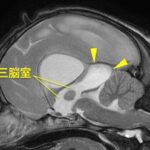

• #2 閉塞性肥大型心筋症ステージB1

循環器科

#2 閉塞性肥大型心筋症ステージB1【循環器科】

<症例情報>雑種猫 2歳7か月齢 去勢済みの男の子 心雑音を認める 主訴:心雑音の精査のた…